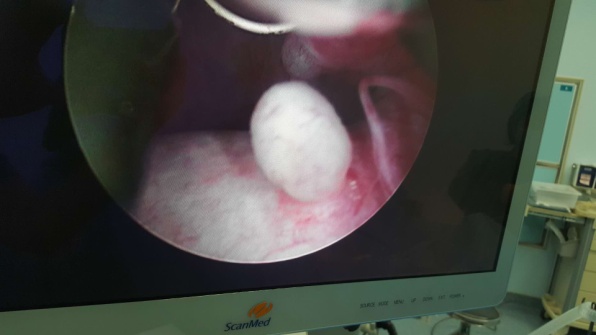

在孙伍柒主任支持、指导下,泌尿外科专家团队制定了详细的手术治疗方案,由雷永刚副主任医师以及李永炜医生成功为患者进行了硬膜外麻醉阴囊镜下左侧睾丸鞘膜切除术,手术切口只有1cm,术中发现睾丸还有一附件,睾丸附件易扭转并导致疼痛等急症,为防止以后附件扭转予以镜下一并切除。术后第3天患者康复出院。出院时患者非常满意。

据介绍,传统的阴囊内手术是在阴囊壁做一个5-12cm的长切口,然后再将病灶切除、缝合切口,该手术切口长、创伤大,易继发伤口感染,恢复慢,住院时间长。而阴囊镜微创手术只须在阴囊皮肤上做一个0.5-1.0cm长切口,整个手术过程直观、精细,创伤小,恢复快,伤口小,术后仅需缝合0-1针,住院约3-5天。